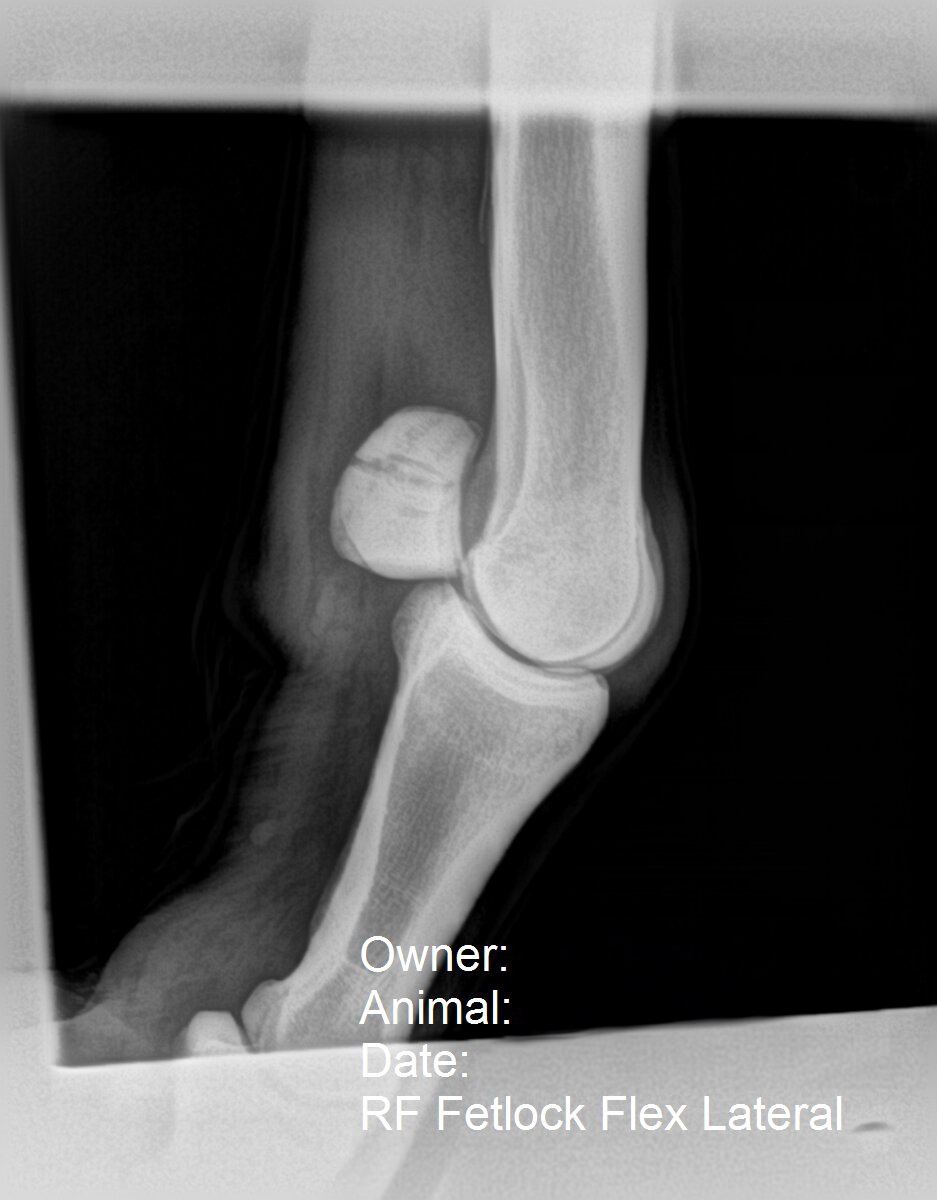

Veterinarians also diagnose sesamoid fractures in racehorses—affecting one or both sesamoid bones at the back of the fetlock, which are surrounded by ligaments. These injuries range in severity and can be tricky to repair because many possible fracture configurations exist (i.e., different parts of the bone can break in many ways).

Sesamoid fractures happen in sport horses, too—like any fracture, whether during work or turnout—but usually are simple fractures compared to what is sustained at high speed. Overall, sesamoid fractures are more often seen in racehorses versus other types of performance horses, says Allday.

In this radiograph, the right front fetlock is flexed, and fracture to the sesamoid bone is visible. Courtesy Danielle Montgomery